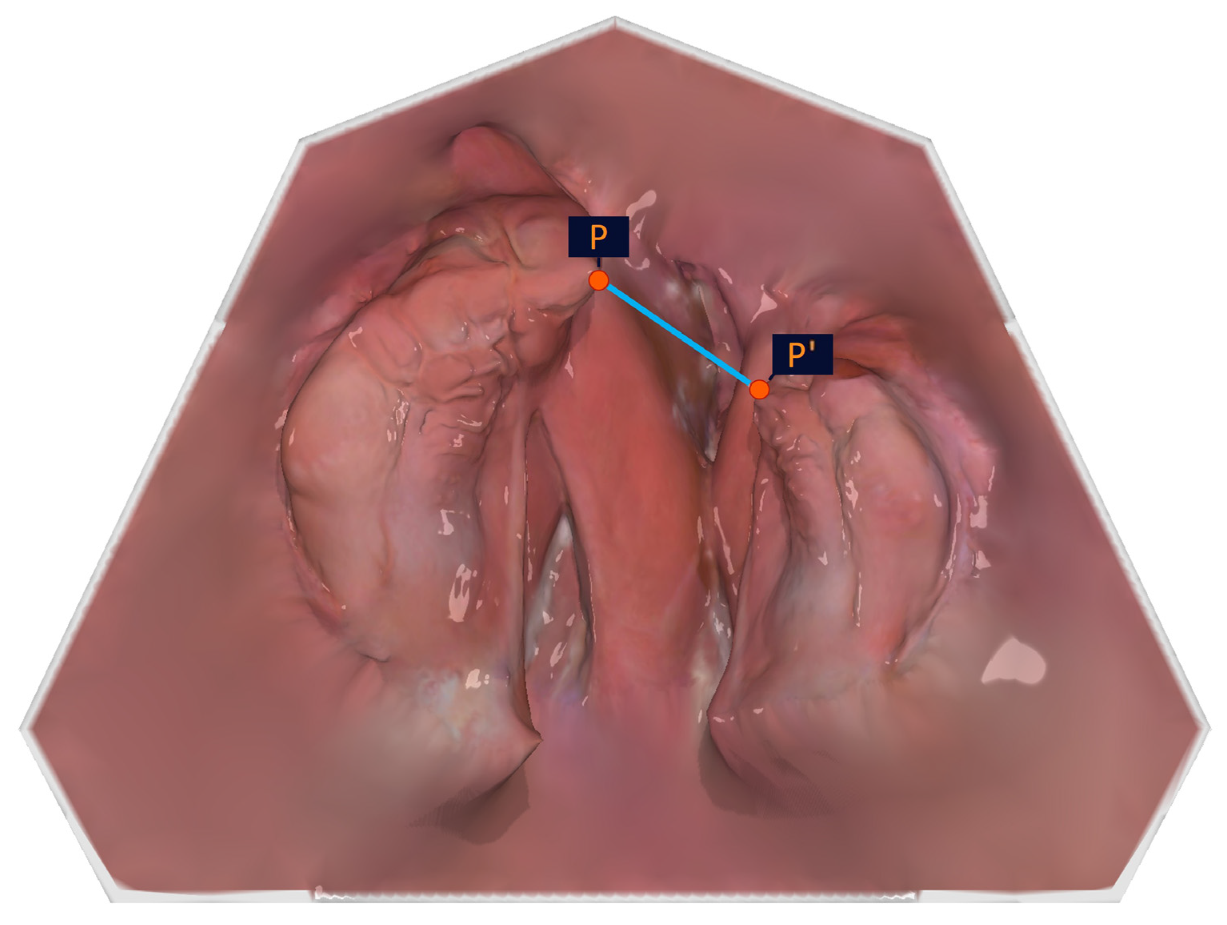

The measurement points of the alveolar cleft width are shown in Table 4 and Figure 7.

As the cleft edge of the crest of the alveolar ridge (large/small segment; P1/P2) does not represent the shortest distance between the large and the small segments in the pole region, it was important to the authors to include the outermost and foremost points of the alveolar ridge (points P and P′) in the analysis, which describe the closest approach of the segments.

Figure 7. Illustration of the measuring points of the alveolar cleft width.